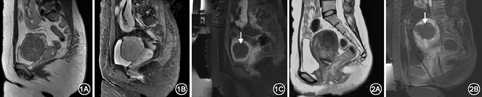

治疗结束后静脉注射钆特酸葡胺进行增强扫描,病灶中不强化的区域称为非灌注区(图1),其病理基础为凝固性坏死[7]。采用累积体积法计算子宫肌瘤或腺肌症体积和非灌注体积(nonperfused volume,NPV),NPV与子宫肌瘤或子宫腺肌症总体积的比值为非灌注体积比(nonperfused volume ratio,NPVR)。计算消融效率,计算公式为:消融效率=NPV/超声辐照时间,超声辐照时间为该患者治疗中超声持续发射时间之和。

终止治疗者8例,包括肌瘤组4例和腺肌症组4例,原因:1例病灶前方有肠管阻挡,经肠管处理仍无安全治疗路径;6例升温不佳,试验治疗10~15个靶点中有80%以上的靶点温度未能上升至65 ℃或以上,预计消融效果较差;1例使用较低的治疗能量即出现明显下肢疼痛,为防止骶神经不可逆损伤予以终止治疗。完成MRgFUS治疗者53例,包括肌瘤组32例和腺肌症组21例,治疗完成率分别为88.9%和84.0%(χ2=0.31,P>0.05,Fisher的精确检验)。肌瘤组和腺肌症组主要治疗参数见表1。肌瘤组和腺肌症组的NPVR均>50%(图1,图2)。